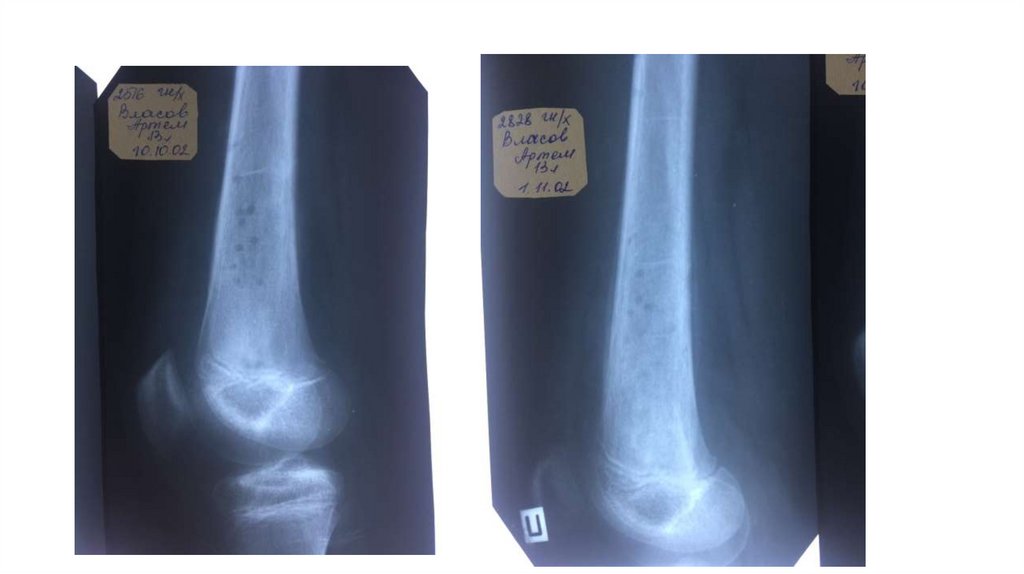

Воспалительные заболевания опорнодвигательного аппарата

«Воспалительные

заболевания опорнодвигательного аппарата»